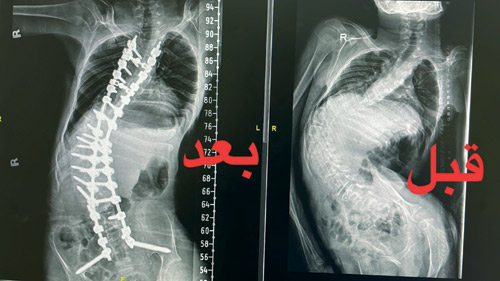

تمكن فريق طبي في مدينة الملك فهد الطبية إحدى مكونات تجمع الرياض الصحي الثاني، من تصحيح جزء كبير من الجنف «شلل دماغي» وهو ضمور في المخ من الدرجة الثالثة لمريض في العقد الثاني من عمره، ومساعدته على الجلوس مرة أخرى بعدما كان غير قادر على الجلوس بسبب الجنف الشديد الذي تعدى 140 درجة.

وبيَّن الدبيان أن المريض تمكن من المشي مرة أخرى بعد العملية بـ 6 أشهر باستخدام المشاية، وقد فقد القدرة على الجلوس والمشي بسبب الزيادة في درجة الانحراف، مما أدى إلى اختلال توازنه، وعدم تمكنه من الجلوس والمشي دون مساعدة.